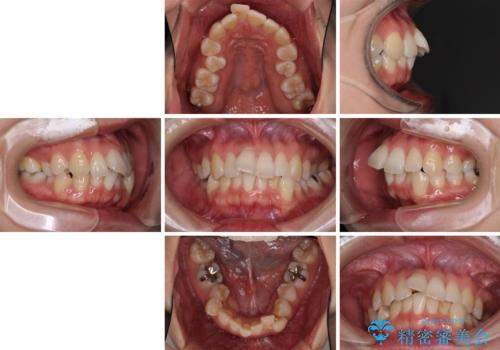

- 上下の歯の前後関係が乱れ、歯に負担がかかるとのことで来院された患者様です。

下顎が右左側に変位しているため、左側奥歯の咬み合わせが上下反対の関係となっていました。

また、上下ともに歯列が狭窄しており、奥歯以外にも反対咬合が認められました。

歯列全体の拡大と、歯と歯の間を削ることでスペースを獲得し、インビザラインによる矯正治療を行うこととしました。

骨格的な問題を抱えた左奥以外は比較的早く咬み合わせが改善しましたが、左奥はどこで咬み合えば良いのか分からず、大変不便な思いをされていました。

ゴムかけにご協力いただき、最終的には反対咬合を改善することができ、患者様には大変満足していただきました。